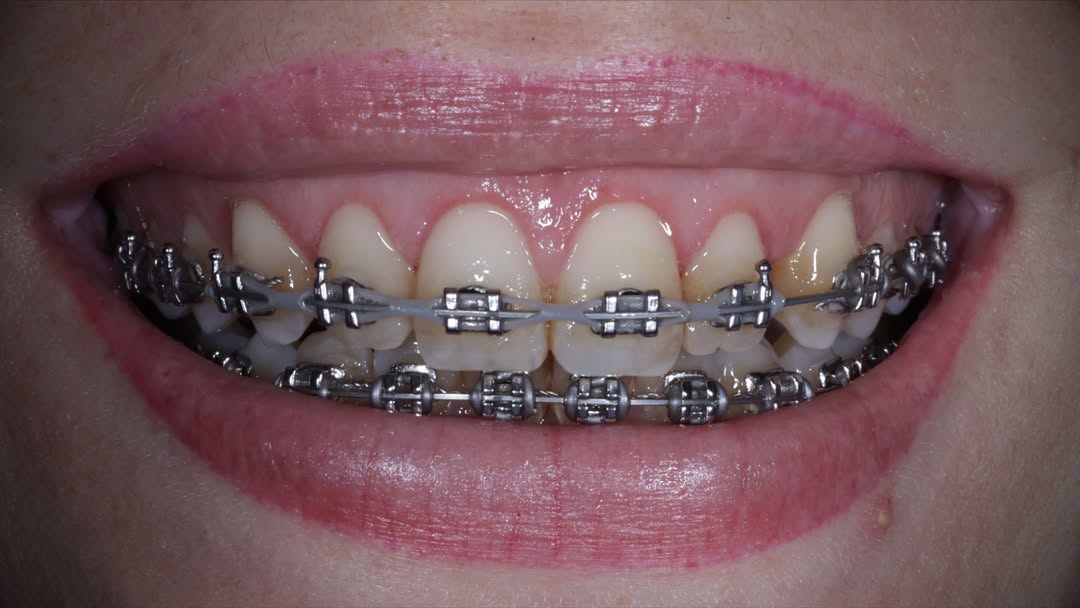

Se presenta un caso clínico de restauración directa en resina composite, ejemplo del valor de la precisión y la técnica meticulosa incluso en procedimientos considerados rutinarios dentro de la práctica diaria. El caso pone en evidencia la importancia del control de la morfología, la textura y la integración cromática, así como del adecuado aislamiento del campo operatorio y la estratificación del material, factores determinantes para conseguir un resultado natural, funcional y duradero. A través de una ejecución cuidadosa, se logró una restauración estéticamente imperceptible y funcionalmente estable, que respeta los principios de mínima invasión y adhesión efectiva. Este tipo de procedimientos, aunque cotidianos, reflejan la constancia y el nivel de exigencia clínica necesarios para ofrecer odontología de calidad en todos los casos, independientemente de su complejidad.